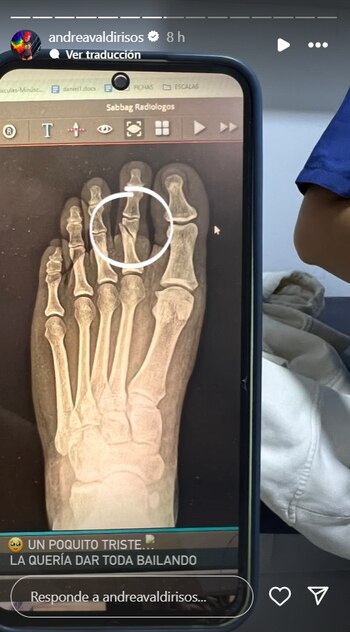

La influencer Andrea Valdiri tuvo un accidente en su casa que la llevó asistir de emergencia a sala de urgencias. El incidente, ocurrido en su casa en Barranquilla, la dejó con una fractura en un dedo del pie derecho, según ella misma reveló a sus seguidores a través de sus historias en Instagram. La fractura se produjo tras tropezar con una alfombra, un hecho que ella describió con humor, afirmando que “ni la alfombra de su casa la quiere”.

La creadora de contenido compartió varios videos desde el hospital donde se la ve en una silla de ruedas y manifestó sus preocupaciones laborales. Recordó que tenía un compromiso con la comunidad Lgbtiq+, siendo una figura destacada en la Marcha del Orgullo, programada para el 30 de junio. “Un poquito triste, la quería dar toda bailando”, confesó Valdiri al hablar de su participación en el evento.